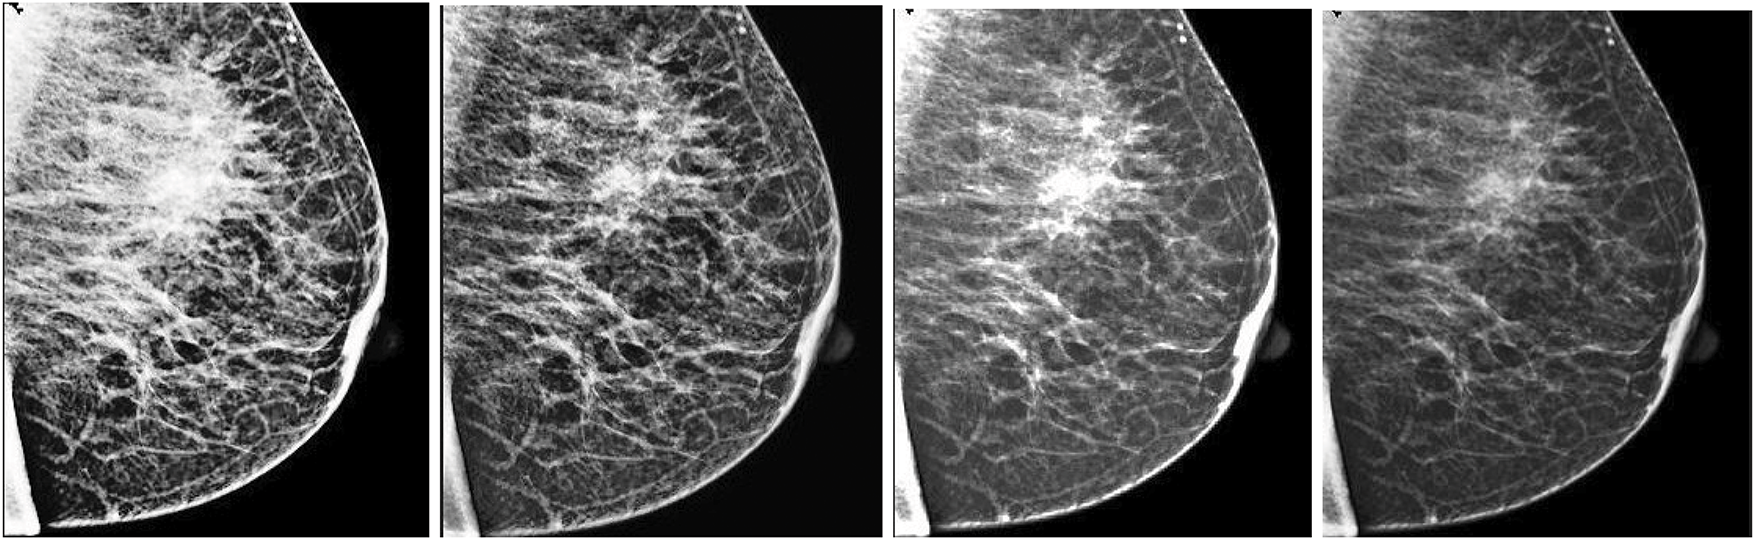

To further validate the effectiveness of our proposed enhancement technique, we conducted a comprehensive comparative analysis against several widely used traditional methods, including Histogram Equalization (HE), Contrast-Limited Adaptive Histogram Equalization (CLAHE), and Wavelet-based enhancement. These techniques are commonly applied in medical imaging to improve visual contrast and emphasize anatomical structures. As illustrated in Table 6, the ICA-based enhancement approach demonstrated superior performance across all evaluation metrics, including segmentation accuracy, contrast-to-noise ratio (CNR), and edge preservation index. Specifically, our method achieved a segmentation accuracy of 94.1%, outperforming Wavelet (91.2%), CLAHE (89.7%), and HE (86.3%). The ICA method also exhibited the highest CNR and the most effective retention of edge information.

Fig. 7 visually compares the output images generated from each enhancement method. It is evident that ICA-enhanced images offer improved clarity and better delineation of breast tissue and lesion structures. These findings suggest that ICA plays a vital role in improving segmentation performance and can serve as a highly reliable preprocessing step in automated mammographic image analysis and computer-aided breast cancer detection systems.

Figure 7: Visual assessment of various enhancement techniques applied to a mammographic image. From left to right: (1) Histogram Equalization (HE), (2) Contrast-Limited Adaptive Histogram Equalization (CLAHE), (3) Wavelet-based enhancement, and (4) Independent Component Analysis (ICA). Among these, the ICA-enhanced image demonstrates the most effective contrast improvement, enhanced lesion boundary definition, and significant noise suppression, making it highly suitable for diagnostic analysis